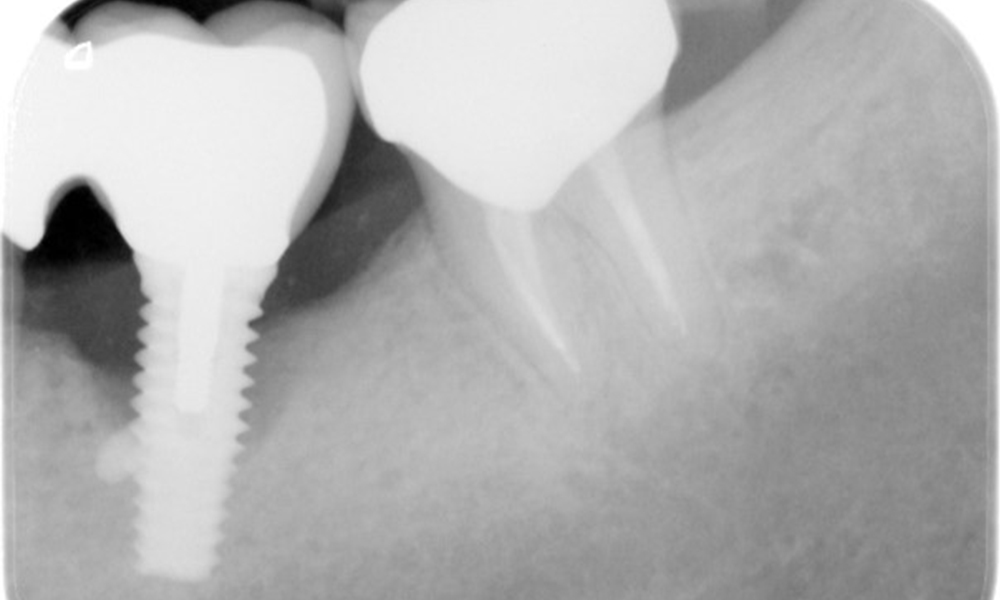

В историята на заболяването на пациента няма особени рискови фактори със специфични дентални последици. Следователно ключовият фактор е изискването по отношение на оралното здраве. В това отношение има данни за дълбочина на сондиране от 5 mm при импланта в 3-ти квадрант, а на рентгеновата снимка - за увеличена костна загуба. Пациентът също така има стабилно понастоящем пародонтално заболяване и две активни начални кариозни лезии.